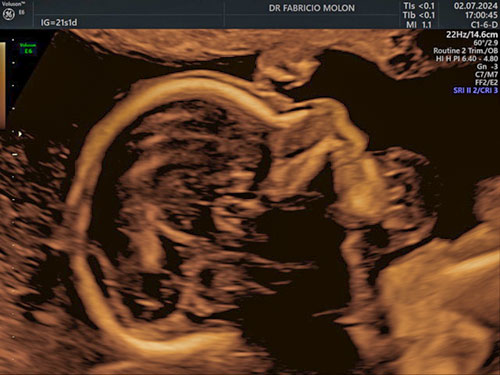

US 3D/4D e 5D com HD live

É possível conhecer o rostinho do bebê ainda na barriga, com a ultrassonografia 4D e 5D! Essa tecnologia permite ver a face do bebê com uma precisão incrível, além de poder gravar as imagens.

O exame traz melhores imagens quando realizado entre 26 e 30 semanas.